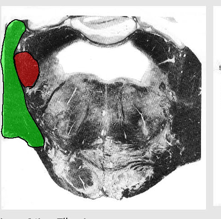

Describe the Inferior/Middle/Superior Cerebellar Peduncles

Locations?

Importance?

inferior cerebellar peduncle (restiform body, ICP)

enter cerebellum in dorsal and lateral position.

Includes:

vestibulocerebellar projections called juxtarestiform body

Middle Cerebellar peduncle:

between the pons and cerebellum

will wrap laterally around the inferior peduncle

superior cerebellar peduncles

in more rostral sections

Forms part of roof of 4th ventricle along with superior medullary velum,

CT membrane between them.